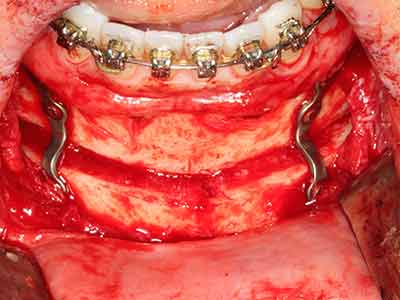

Както е показано в миналото, всяка костна хирургия представлява възможна индикация за пиезохирургия. По този начин, за препарацията на подвижни сегменти в остеогенеза (Фиг. 23-25) и остеотомия се използват специални накрайници, без да се застрашава снабдяването с кръв в кресталната зона, което е от съществено значение за успеха и на двете техники (Gonzalez-Garcia, Diniz-Freitas et al. 2008).

Чисто ортодонтските индикации включват ортогнатна хирургия, генопластика (Фиг. 27-30) и орбитална декомпресия при пациенти с напреднала ендокринна орбитопатия, в резултат от Базедова болест (Ponto, Zwiener et al. 2014). Пиезо апаратите се използват също за лицево-челюстна хирургия и за отстраняване на тумори в основата на черепа в различни болници.